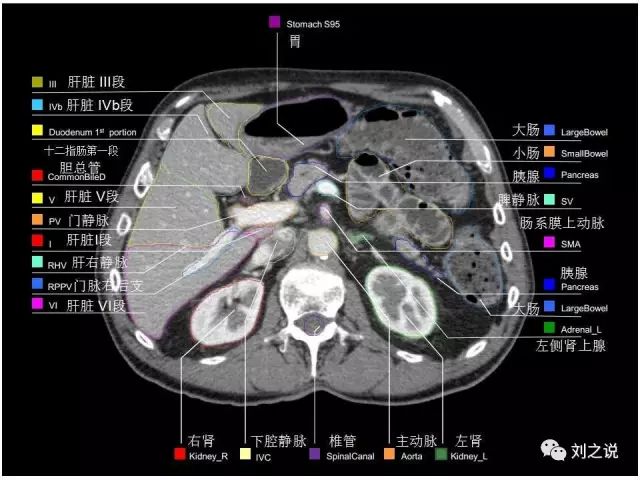

参考RTOG共识和3D-body解剖。

来源:刘之说